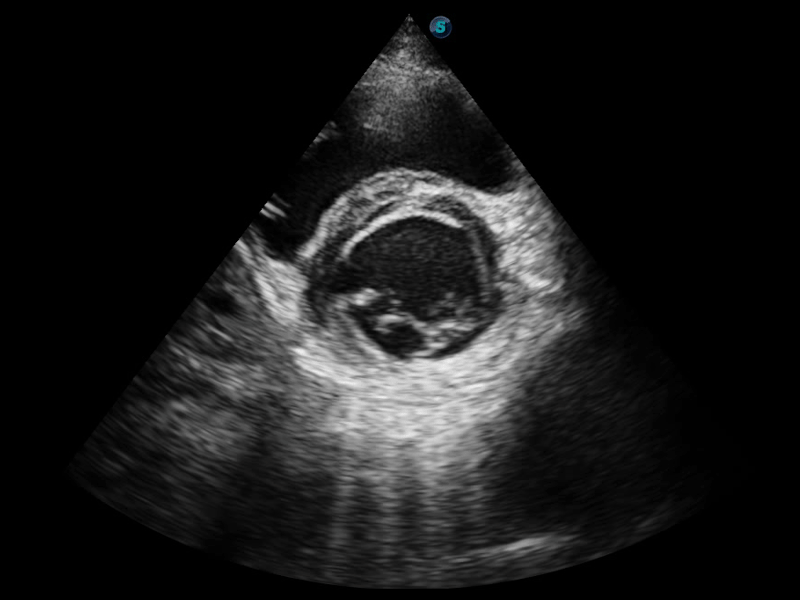

開立醫(yī)療通過不斷的技術(shù)創(chuàng)新,為大眾的生命健康提供持續(xù)關(guān)愛。P12 Plus采用全新一代超聲成像平臺,新平臺旨在將真實(shí)還原組織解剖結(jié)構(gòu)作為首要目標(biāo)。平臺采用全新集成化硬件模塊,搭載新一代芯片,系統(tǒng)性能得到大幅提升,為您的診斷提供了豐富的臨床信息。優(yōu)異的圖像表現(xiàn),豐富的探頭配置,全面的應(yīng)用功能,為您日常診斷提供了可靠的助手。

彩色多普勒超聲診斷系統(tǒng)